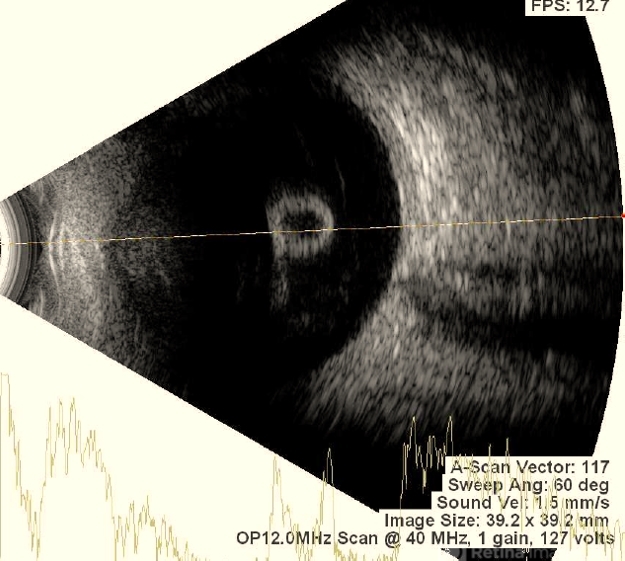

- Vitreous Cyst

- vitreous cyst, Vitreous hemorrhage, retinitis pigmentosa

- Imaging device

- Ultrasonography device

- This picture shows RE USG of a 30 year old female with vitreous cyst with spontaneous vitreous hemorrhage in a case of retinitis pigmentosa.